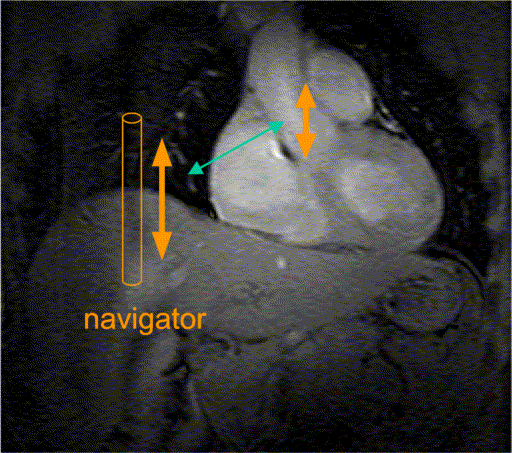

Figure 2. Respiratory gating: Respiratory motion of the right

hemidiaphragm is measured during the examination. A linear correlation

between motion of the diaphragm and the heart is assumed. Acquired data

is only accepted if the navigator position is in the respiratory gating

window. Otherwise data is rejected and has to be remeasured.